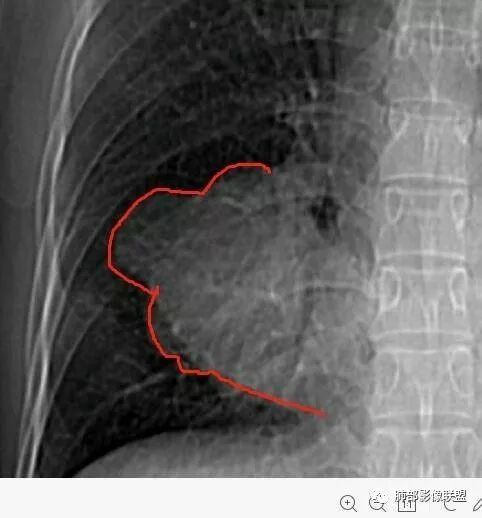

南边:深分叶、大肿块

南边:边缘膨隆

南边:病灶边界清,提示侵袭性弱,膨胀生长为主;这时候我们提示病灶不应该是支气管关系密切,提示间叶来源或胸膜来源

深分叶,警惕恶性

常规考虑:1、肉瘤首先考虑

3.肿块常常较大,甚至巨大,病灶边界一般清楚,影像上常有假包膜样结构、有膨胀性生长的特点,影像科医师有时甚至会纠结其来源于肺部或是胸壁纵隔。常见的肺癌肿块,很少有机会能长成这样的规模。

4.边缘可以有浅切迹,部分病灶会有铸型样外观,但大体十分圆钝,不会出现典型的分叶和毛刺,也很少会出现胸膜牵拉。支气管常推移,有明显的支气管阻塞时也较少观察到相关的阻塞性炎症。

5.病灶密度大多不均,不规则坏死液化,少数病例出现钙化。增强扫描常观察到由外而内的厚壁不均匀强化,中央半岛样强化等等,厚壁中或实性区常能显示血管影。一些病灶中央呈现边界清楚囊样变。